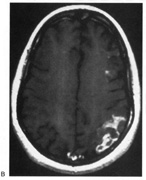

Fig. 5. Macula-splitting hemianopia. A 47-year-old man with AIDS and sudden onset of poor vision. A. Fields show complete left hemianopia. B. MRI shows lesion of right lateral occipital cortex, affecting distal optic radiations. Biopsy showed nonspecific encephalitis.

Fig. 6. Lesion of temporal optic radiation. Left superior quadrantanopia, respecting horizontal meridian (A), from infarct of right medial temporal lobe, in posterior cerebral artery territory (B). (From Rosen ES, Eustace P, Thompson HS, Cumming WJK [eds]: Neuro-Ophthalmology. London: Mosby, 1998.)